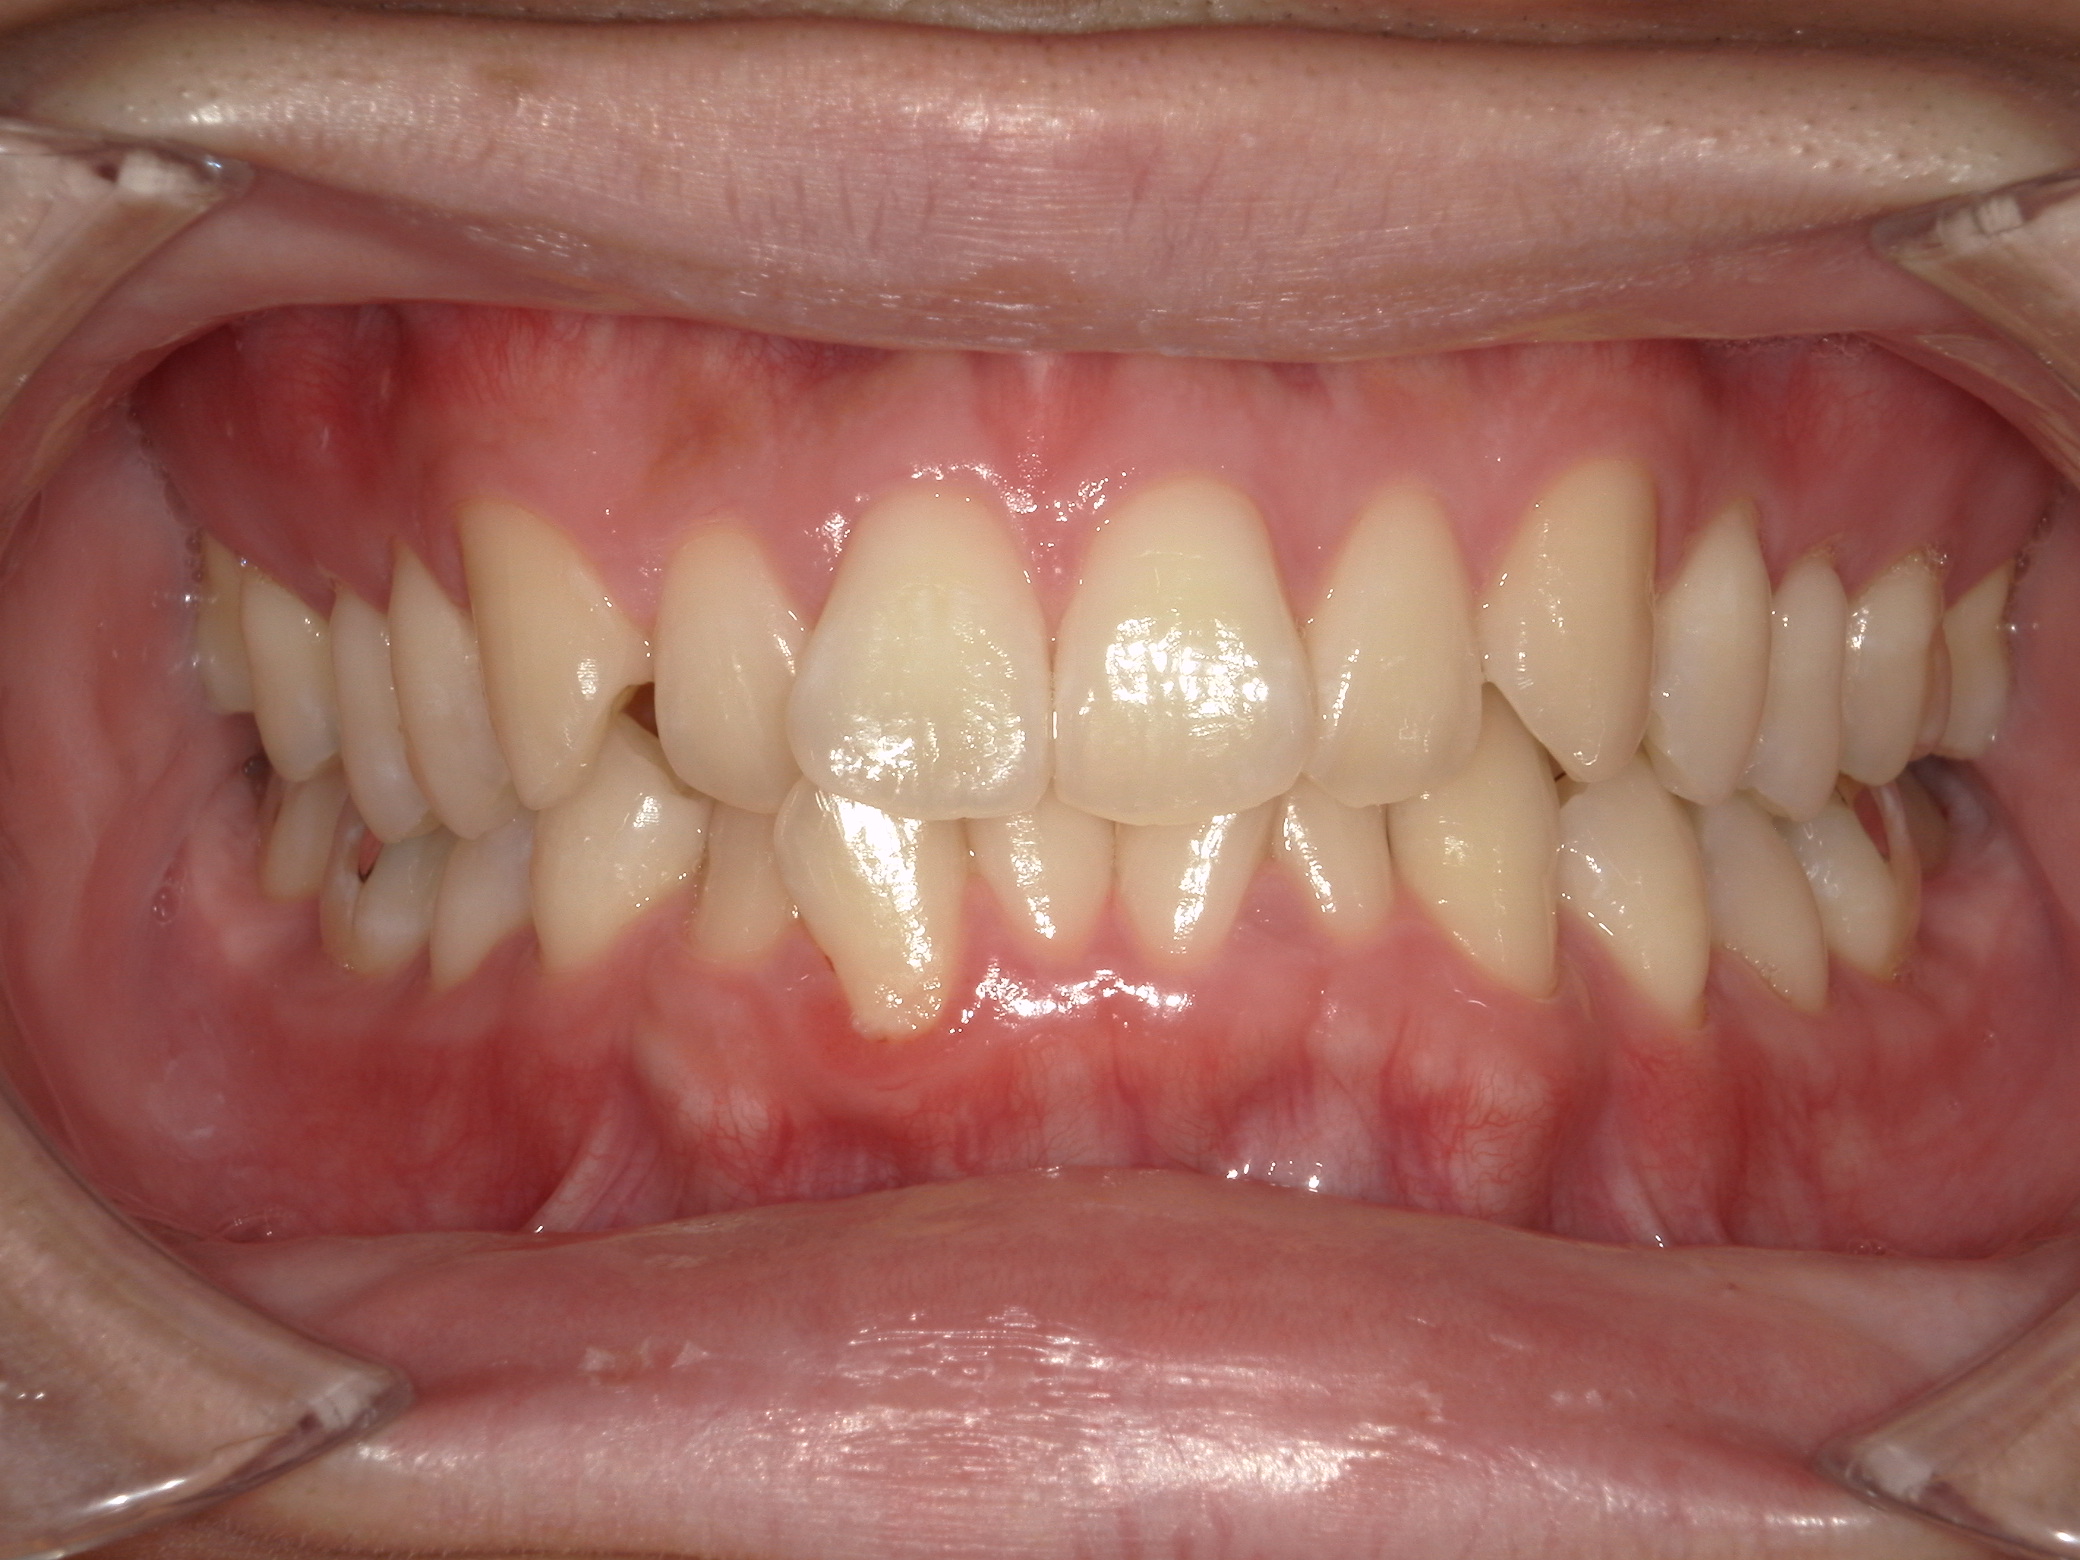

治療前

治療後